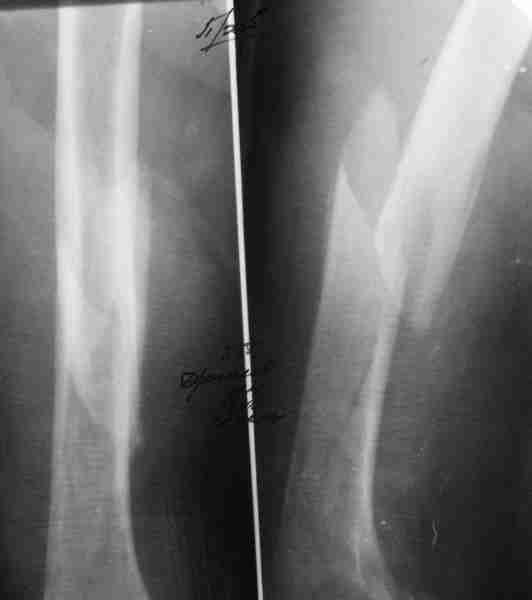

С оскольчатым переломом правой бедренной кости. Травма 27 декабря 2013. В районной больнице был уложен на систему скелетного вытяжения, на которой пребывал до начала февраля(стояние костных фрагментов было более чем хорошее), после чего в начале февраля переведен на фиксацию гонитной гипсовой повязкой, через 2 недели на рентгенконтроле имеется смещение костных фрагментов в гипсовой повязке(на снимках). В анамнезе у больного выраженный атеросклероз сосудов обеих нижних конечностей с трофическими расстройствами мягких тканей пальцев травмированной ноги (на фото), большой стаж курения более пачки в день (сейчас уже не курит).По данным заключения допплер имеется окклюзия передней большеберцовой артерии справа, подколенной артерии, с достаточно хорошо выраженной системой коллатералей.Флотирующих тромбов не обнаружено, в основном старые бляшки, больше сосуды изменены на неповрежденной ноге (но трофическиих расстройств на ней нет). Трофические изменения на пальцах стопы появились вскоре после травмы и в настоящий момент без отрицательной динамики. Сосудистый хирург терапию назначил, пациент получает. Планируется ретроградный интрамедуллярный блокируемый остеосинтез бедренной кости с предварительной фиксацией в дистракторе по Челнокову А.Н... Или по другому?

Ув. Алексей! На мой взгляд гвоздь именно потому, что у пациента кровоснабжение дистальных отделов конечности больше за счет коллатералей, именно поэтому гвоздь, а не пластина (кровить будет - мама не горюй, да и коллатерали травмировать не хочеться), а ретроградно, на снимке не очень видно, потому что крупный осколок по передней поверхности идет практически до мыщелка.